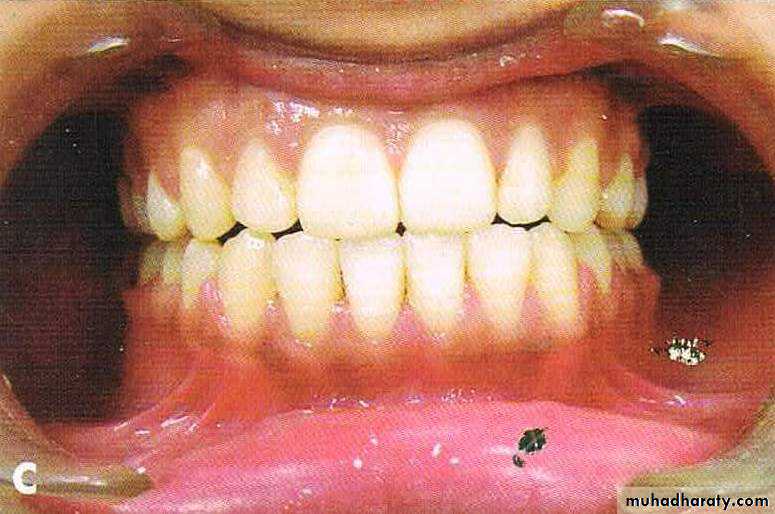

Bimaxillary protrusion

Bimaxillary proclination: the teeth are proclined on normal bases

Bimaxillary protrusion or bialveolar protrusion refers to a protrusive dentoalveolar position of maxillary and mandibular dental arches that produces aconvex facial profile .Bimaxillary prognathism: the jaws/basal bones are forward relative to the cranial base

Features

• Soft tissue• Convex facial form.

• Reduced lip length.

• Lips incompetency.

• Low lower lip line and high upper lip line

• prominent lips.

• Receded chin.

• Dental

• Dental bimaxillary proclination• Larger dental arch length with resultant spacing and diastema

• Normal or increased OJ

• Variable molar relationship but usually normal.

Before & After Treatment